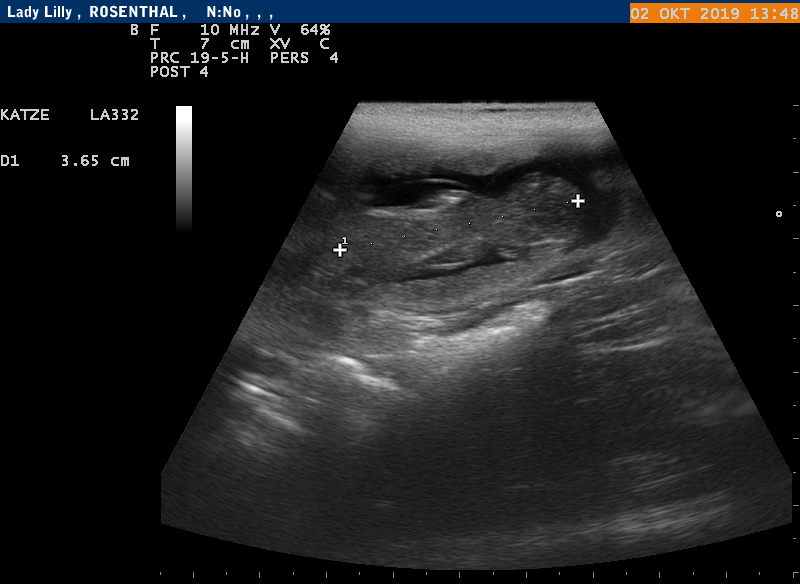

Trächtigkeitsultraschall